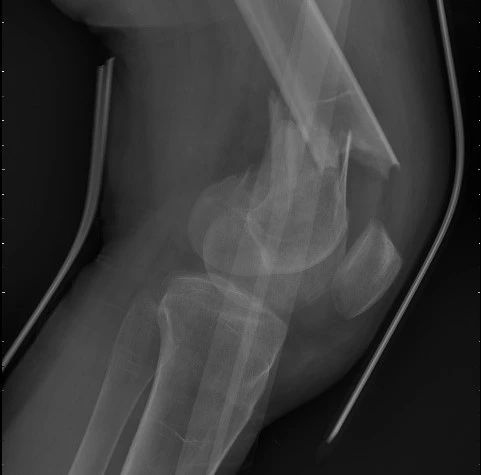

(股骨骨折术前)